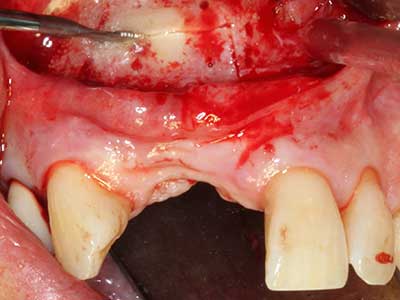

Come descritto in precedenza, le indicazioni per la piezochirurgia si possono trovare anche nel campo della chirurgia odontoiatrica conservativa. Delle puntine particolari semplificano l'esposizione delle punte delle radici e facilitano la protezione dei nervi e delle membrane mucose del seno, in particolare nella regione dentale superiore e posteriore e in quella premolare inferiore. Le puntine angolate diamantate si utilizzano per preparare con precisione la cavità della resezione che ospiterà il materiale di riempimento della radice retrograda per l'otturazione apicale sigillata. Grazie alla tecnologia a ultrasuoni le puntine possono essere estremamente sottili, quindi la visibilità e le dimensioni di accesso della cavità sono migliori. Di conseguenza, l'applicazione della chirurgia a ultrasuoni per questa indicazione è una delle procedure standard per la resezione apicale (Del Fabbro, Tsesis et al. 2010, Scarano, Artese et al. 2012).

Indicazione: resezione apicale